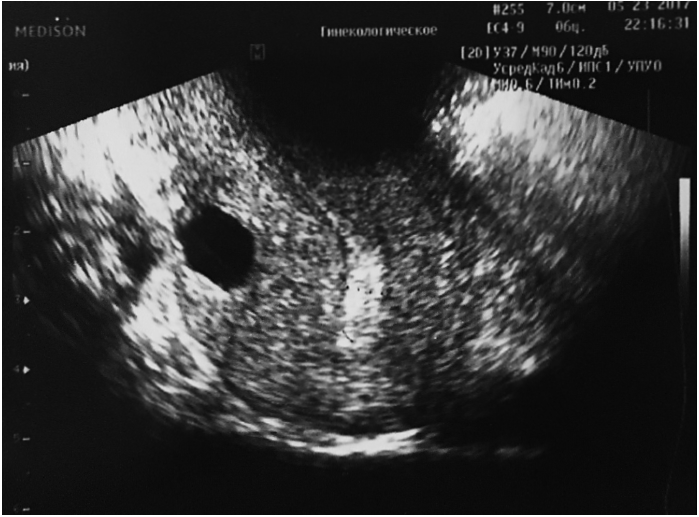

На фоне приема диеногеста через каждые 50–60 дней появлялась фолликулярная киста правого яичника 18–20 мм в диаметре. При этом кистозная анэхогенная полость увеличивалась на 2 мм в диаметре. Через 2 мес функциональная киста исчезала, но кистозная полость в толще матки не уменьшалась. При гипоэстрогенном состоянии, вызванном приемом препарата в течение 9 мес, размер кистозной полости с анэхогенным содержимым в толще миометрия посередине задней стенки матки увеличился до 20 мм в диаметре (рис. 2).

Рис. 2. Узловая форма аденомиоза.

Fig. 2. Nodular form of adenomyosis.